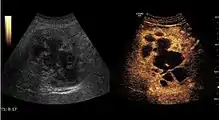

Liver cyst

Hydatid liver cyst. Diagnostic criteria are the presence of membranes and sediment inside.